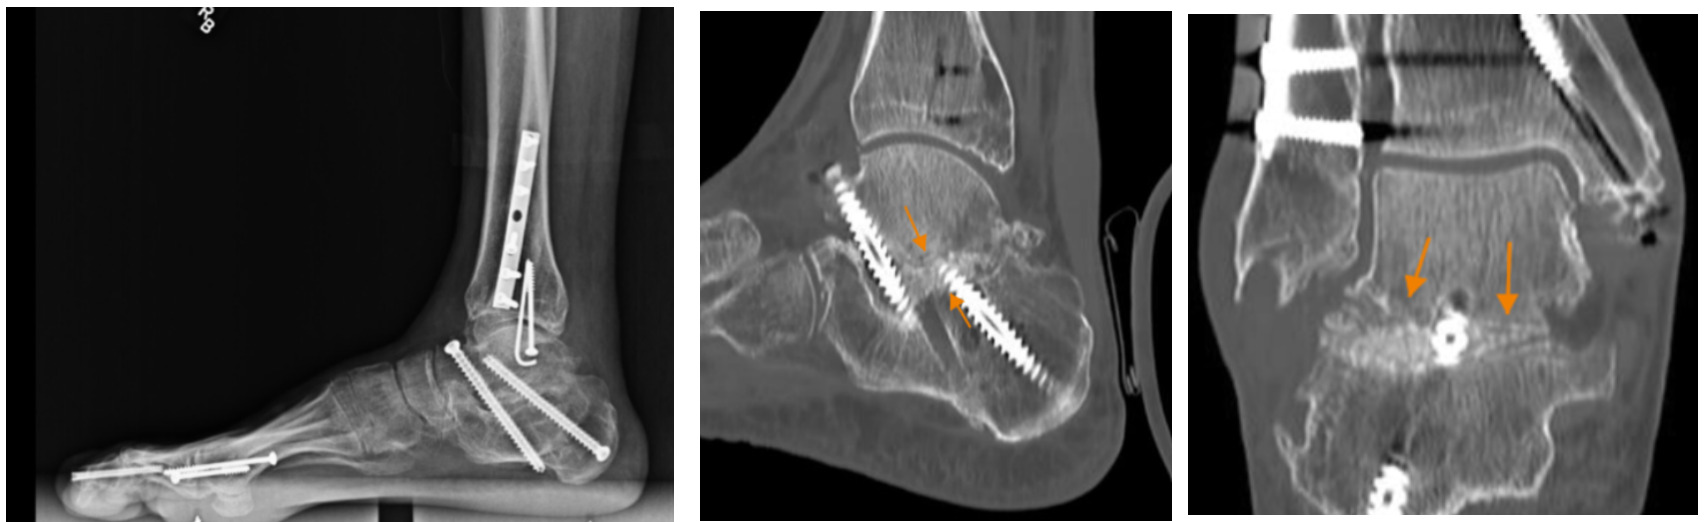

Radiographic evaluation (X-Ray and CT Scans) at this 3-month timepoint showed intact and well positioned screws and evidence of early and complete consolidation of the bone graft (Figure 2). At this point, the patient returned to full weight bearing and was able to walk free of pain with regular shoes. There were no complications noted during surgery or post-operatively.